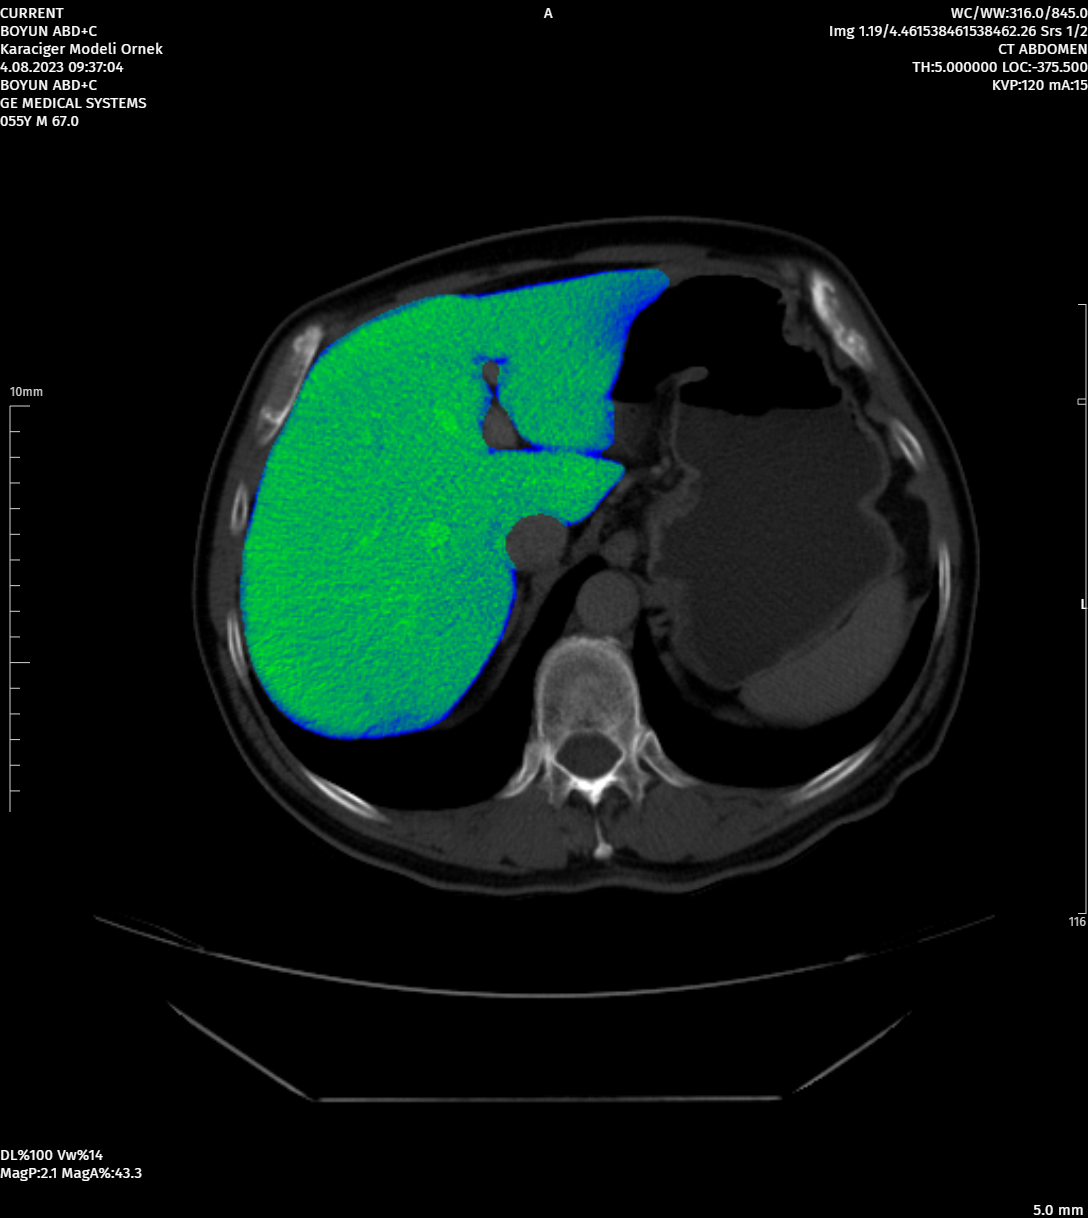

MoreAdvanced Image Processing Tools

Image Processing Tools That Can Work with Different Segmentations